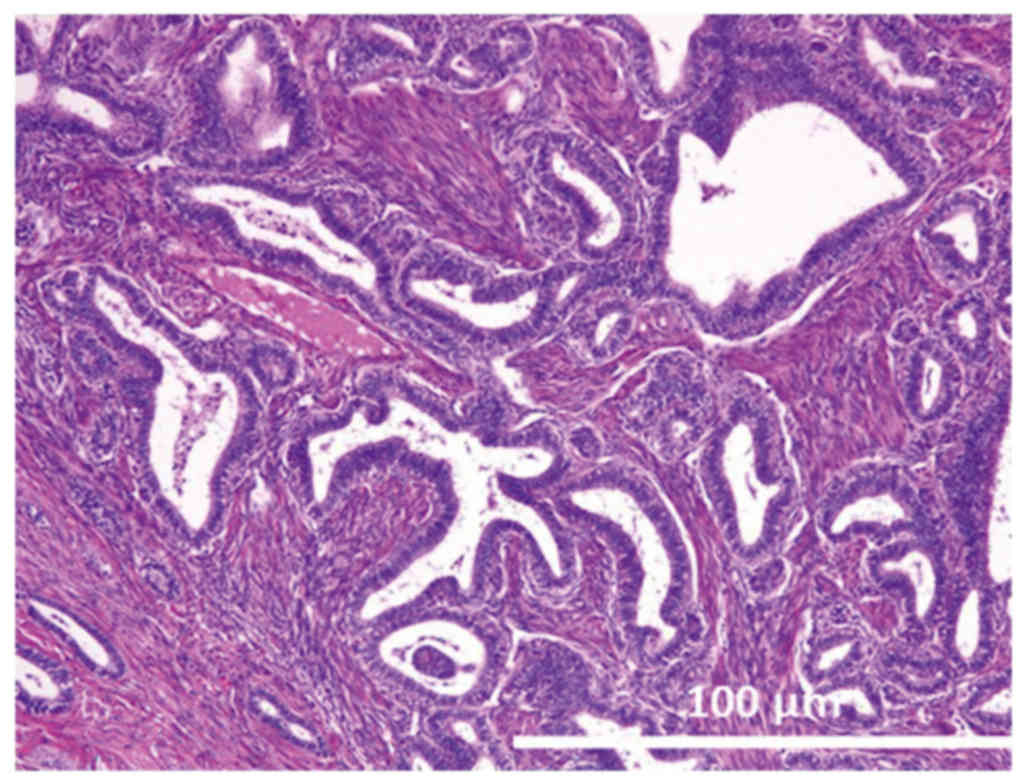

Gross observations of the tumor of the right ovary revealed that it had a maximum diameter of 7.5 cm. Microscopically, the tumor was categorized as having an endometrioid adenofibromatous growth pattern. Numerous glands with intervening fibrous stroma were observed and these glands demonstrated varying degrees of endometrial hyperplasia, ranging from simple hyperplasia to a more marked proliferation, similar to that observed in complex atypical hyperplasia (Fig. 1). No invasion of the ovarian stroma was identified.

Figure 1.

Case 1: Hematoxylin and eosin staining of endometrioid borderline tumor (adenofibromatous type). Mild cytological atypia is present in the endometrioid glands (magnification, ×400).